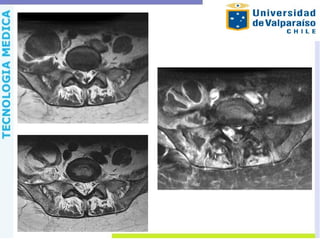

Resonancia Magnética Permite visualizacióny determinación del compromiso de tejidos intraarticulares como cartílago, sinovial y de partes adyacentes como el hueso, ligamentos y músculos, en etapas tan tempranas como a las 24 horas del comienzo de la infección . Sensibilidad cercana al 100% y especificidad del 77% Sensible a: o Daño cartilaginoso temprano o Refuerzo sinovial o Edema peri-sinovial